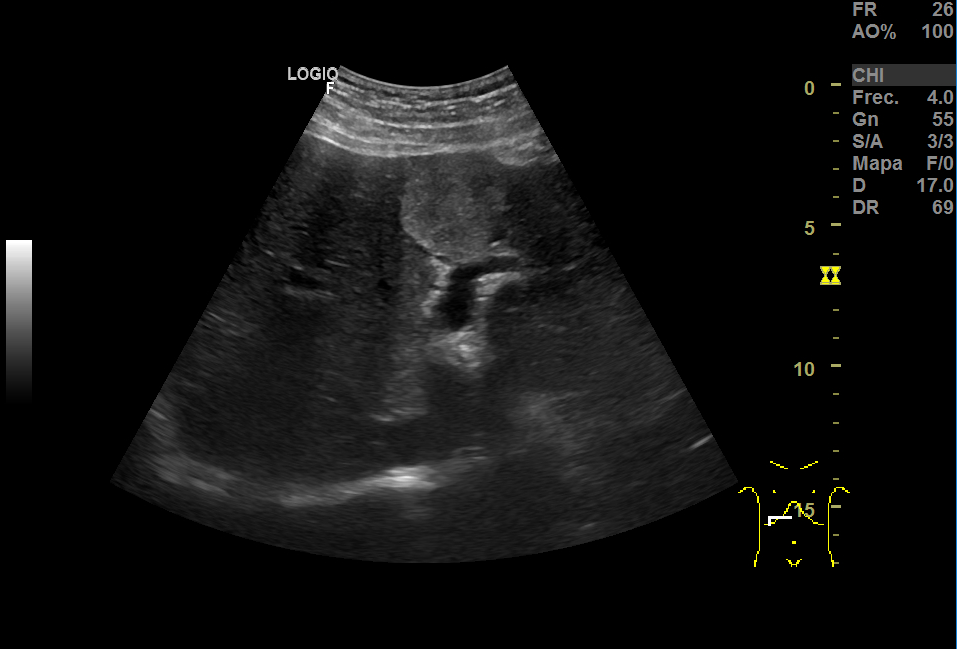

Repite la ecografia: En el segmento IV, aparece una imagen redondeada de 30x40 mm heterogénea, iso-hipoecogénica sin captación ecodoppler que podría ser un angioma, HFN (hiperplasia nodular focal) u otra posibilidad; otra imagen oval hiperecogénica de 19 mm, que sugiere angioma como primera posibilidad.

El aspecto de los hemangiomas hepáticos en la ecografía son lesiones de pequeño tamaño (inferior a 30 mm), hiperecoicas, bien delimitadas, homogéneas, con refuerzo acústico posterior y sin captación en el estudio Doppler. En cambio, el aspecto ecográfico atípico como el de nuestro caso: mayor tamaño, heteroecoico con zona central hipoecoica y límites irregulares o mal definidos, requiere de otras técnicas.

El ecógrafo del centro de salud es una herramienta muy útil que nos ayuda al diagnóstico, pero no nos da el definitivo; para ello, en ocasiones, necesitamos la valoración por Especializada. En este caso, las imágenes hepáticas eran muy sugestivas de LOES tipo metástasis pero la valoración por el Digestivo y la realización de otras pruebas de imagen dieron con el diagnóstico definitivo de hemangiomas.